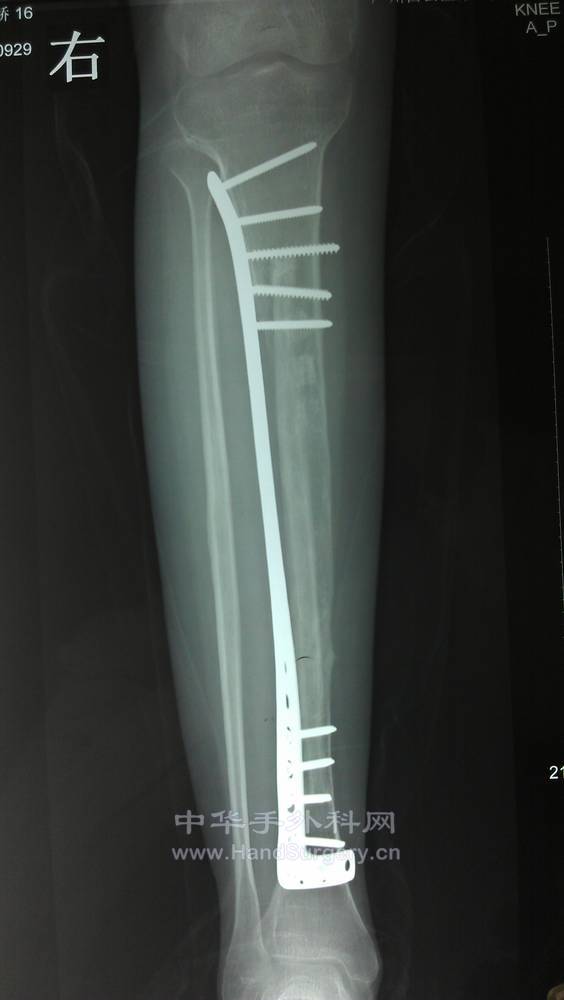

1年后复查的X线片。患者恢复功能很好。

IMAG0177.jpg

IMAG0178.jpg